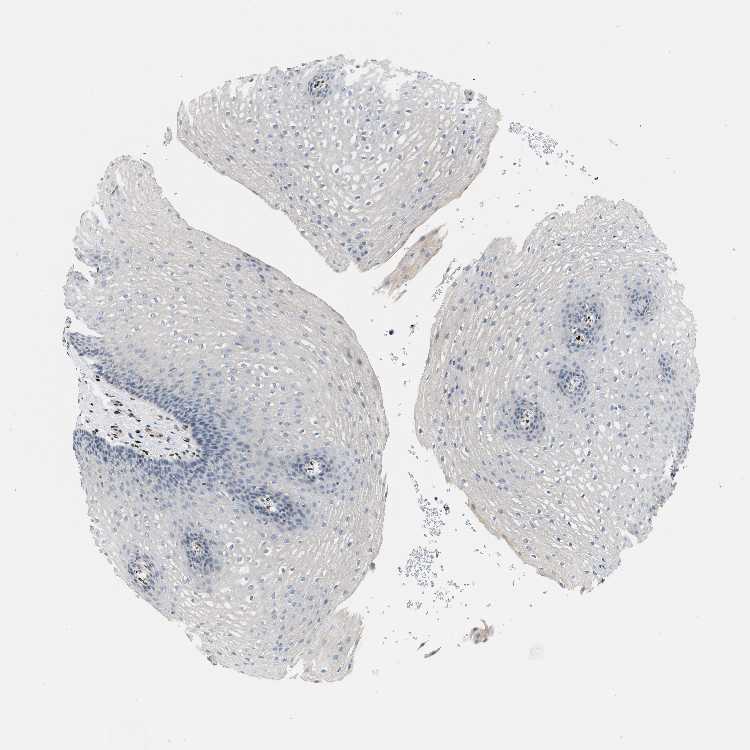

ESOPHAGUS - Antibody stainingi

Antibody staining in the annotated cell types in the current human tissue is reported as not detected, low, medium, or high, based on conventional immunohistochemistry profiling in selected tissues. This score is based on the combination of the staining intensity and fraction of stained cells.

Each image is clickable and will lead to virtual microscopy that enables deeper exploration of all samples and also displays staining intensity scores, fraction scores and subcellular localization as well as patient and tissue information for each sample.

Antibody HPA016815

Squamous epithelial cells Not detected